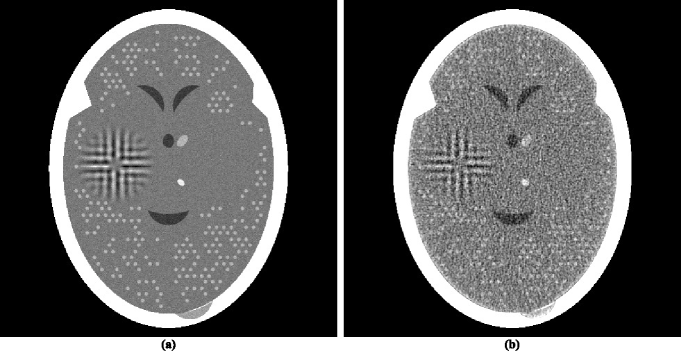

One implementational difference is in the stopping-rule of the iterative algorithm; that is, the choice of ε𝜀\varepsilon in determining the output O(S,ε,RS)𝑂𝑆𝜀subscript𝑅𝑆O\left(S,\varepsilon,R_{S}\right). Since the data are noisy, the phantom itself does not match the data exactly. In previously reported implementations of superiorization it was assumed that the iterative process should terminate when an image is obtained that is approximately as constraints-compatible as the phantom; in the case of the phantom and the projections data on which we report here the value of ResS𝑅𝑒subscript𝑠𝑆Res_{S} for the phantom is approximately 0.91, which is larger than its value (0.33) for the reconstruction produced by ASD-POCS. The output O(S,0.91,RS)𝑂𝑆0.91subscript𝑅𝑆O\left(S,0.91,R_{S}\right) is shown in figure 3(a). This is a wonderfully smooth reconstruction, its TV𝑇𝑉TV value is only 771. However this smoothness comes at a price: we loose not only the ability to detect the large tumor, but we cannot even see anatomic features (such as the ventricular cavities) inside the brain. So it appears that, in order to see medically-relevant features in the brain, over-fitting (in the sense of producing a reconstruction from noisy data that is more constraints-compatible than the phantom) is desirable.

Refer to caption

Figure 3: Reconstructions produced by varying some of the parameters in the algorithm that produced figure 2(b). (a) Changing the termination criterion form ε=0.33𝜀0.33\varepsilon=0.33 to ε=0.91.𝜀0.91\varepsilon=0.91. (b) Changing the value of N𝑁N from 20 to 1. (c) Reconstructing with pixel size 0.752 mm by 0.752 mm instead of 0.376 mm by 0.376 mm. (d) Reconstructing with all the three changes of (a)-(c).

In the implementations that produced previously reported reconstructions by superiorization, the number N𝑁N in the Superiorized Version of Algorithm 𝐏𝐏\mathbf{P} was always chosen to be 1. It is possible that this is the wrong choice, making only this change to what lead to the reconstruction in figure 2(b) results in the reconstruction shown in figure 3(b). That image appears similar to the image in figure 2(b), but it has a higher TV𝑇𝑉TV value, namely 832, which is still very slightly lower than that of the ASD-POCS reconstruction. The choice N=20𝑁20N=20 was based on the desire to maintain consistency with what has been practiced using ASD-POCS, see page 4790 of SIDK08a (42). It appears that in the context of our paper the additional computing cost due to choosing N𝑁N to be 20 rather than 1 is not really justified. (We note that if 𝒅𝒅\boldsymbol{d} is selected using subgradients as discussed in the paragraph following (7) and thus 𝒅𝒅\boldsymbol{d} is not guaranteed to be a nonascending vector for the TV𝑇𝑉TV function, then the choice of 20 rather than 1 for N𝑁N results in a considerable improvement. However, an even greater improvement is achieved even with N=1𝑁1N=1 by selecting 𝒅𝒅\boldsymbol{d} as recommended in this paper.)